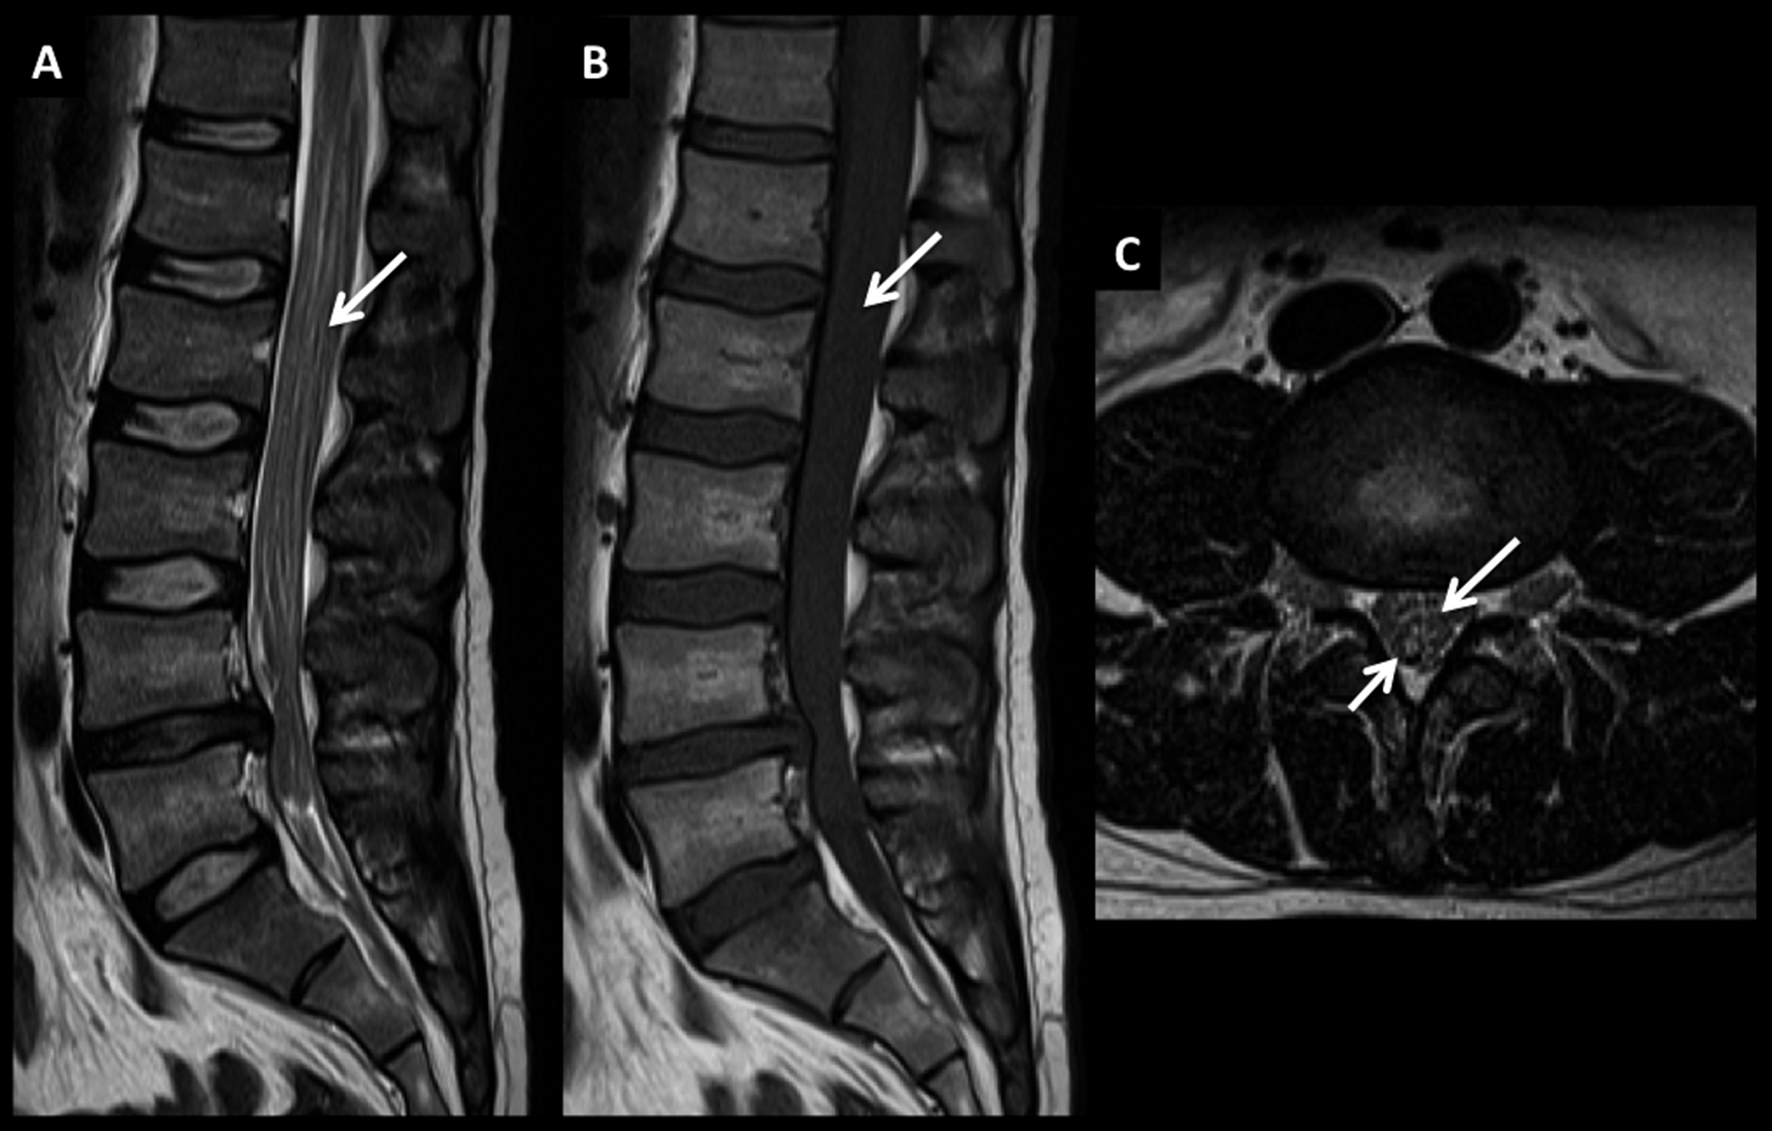

Figura 6

LNH, masa intrarraquídea extradural, compromiso primario.

Imágenes seleccionadas de un paciente joven con un síndrome de cola de caballo progresivo con intenso dolor. En el plano sagital T2 (A) se observa una extensa masa sólida intrarraquídea intradural, extramedular, de señal intermedia.

En T1 (B) la misma es homogénea de baja señal con alta señal en STIR (C).

Luego de administrar medio de contraste presenta un intenso y homogéneo realce (D).

Se confirma el diagnóstico luego analizar una muestra del tejido obtenido en cirugía de degravitación del conducto raquídeo.